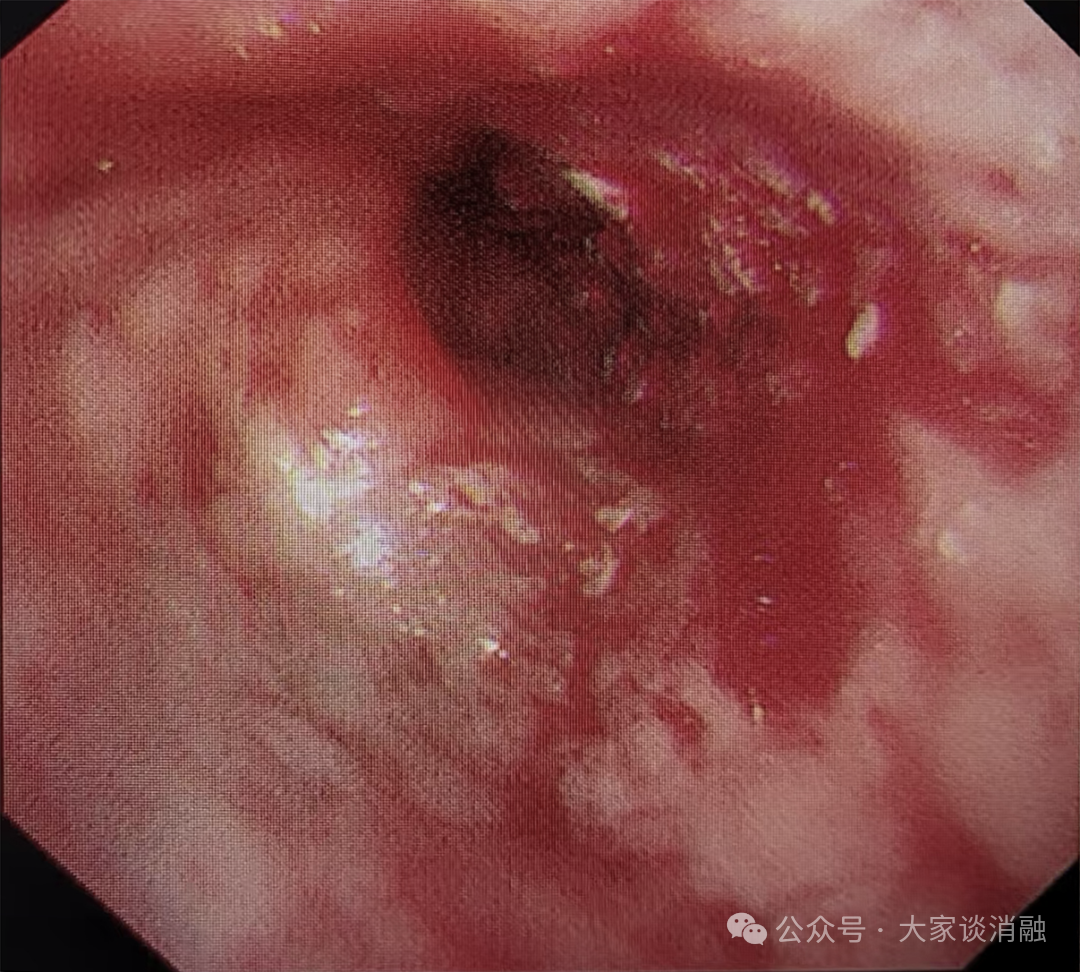

第二次治疗

10月24日,邵桂英主任团队为患者进行术后第一次局麻下清坏死组织治疗气道内的肿瘤体积进一步缩小,下叶开口管腔越来越通畅,原本严重的呼吸困难及持续咳嗽症状也明显减轻,患者及家属对治疗效果十分认可

术后